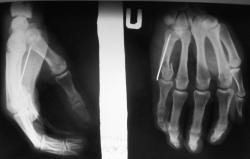

Да нет, Валентин Львович, не зажимала я )))))). Я этот случай выставляла на "радиографии", еще когда результаты не были известны. Я, в первую очередь, думала о туберкулезе. Но...результаты гистологии были неожиданны для всех - эозинофильная гранулема. Если хотите, посмотрите тут http://radiographia.ru/node/1792 , там есть и КТ.

Валентин Львович, я думаю, что гистологи, все-таки, правы. Можно было бы и самой это предположить, ведь я потом вспомнила, что года два назад у нас была девочка, такого же возраста, только с левым т/б суставом, изменения аналогичные, по рентгенограммам - один в один, но КТ тогда еще не было. Там тоже была эозинофильная гранулема, просто тот случай совсем вылетел из головы. И в данном случае снова все зациклились на туберкулезе.

A что Вам не нравится в случае с пястной костью?